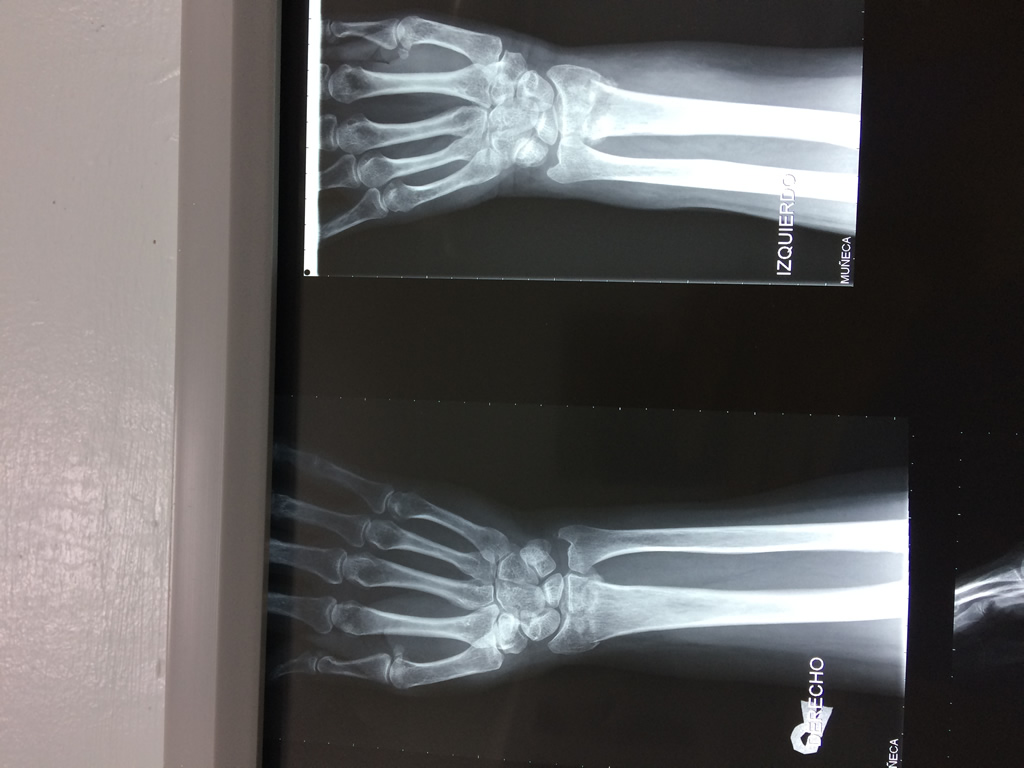

Cirugías de Hombros - Cirugías de Muñecas y Manos

Los procedimientos más comunes en cirugía de la mano son aquellos destinados a reparar traumatismos, incluyendo lesiones de tendones, nervios, vasos sanguíneos, y articulaciones; huesos fracturados; y quemaduras, cortes, y otros daños de la piel.